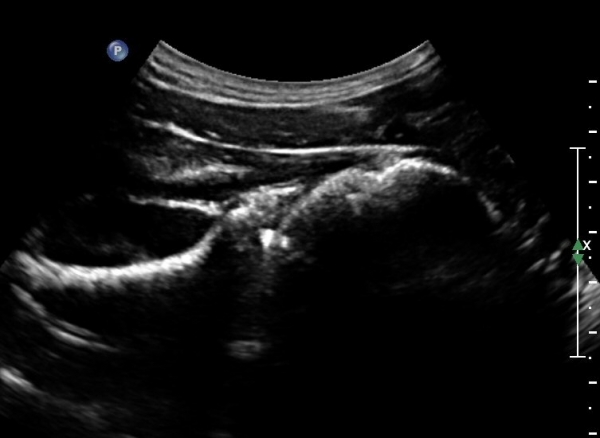

ÃÊÀ½ÆÄÀ¯µµÇÏ ÈíÀÎÄ¡·á Áß ÁÖ»ç¹Ù´ÃÀÌ ¼ö¾×³»¿¡ Á¤È®È÷ À§Ä¡ ÇÑ °ÍÀÌ °üÂûµÈ´Ù(»çÁø 7).

ÃÊÀ½ÆÄÀ¯µµÇÏ ÈíÀÎÄ¡·á ÈÄ ´ëºÎºÐÀÇ ¼ö¾×ÀÌ Á¦°Å µÈ °ÍÀÌ È®ÀεȴÙ(»çÁø 8).

º» Áõ·Ê¿¡¼­´Â 22G¹Ù´Ã·Î ÈíÀÎÀÌ ¾ÈµÇ¾î 18G ¹Ù´Ã·Î ¾à 5cc ¼ö¾×À» ÈíÀÎÇÏ¿´À¸¸ç

ÈíÀÎ ÈÄ Áï ½Ã Áõ»çÀÇ È£Àü°ú  ¼öµ¿Àû ³»Àü ½Ã ÅëÁõÀÌ ¼Ò½ÇµÇ¾ú´Ù.